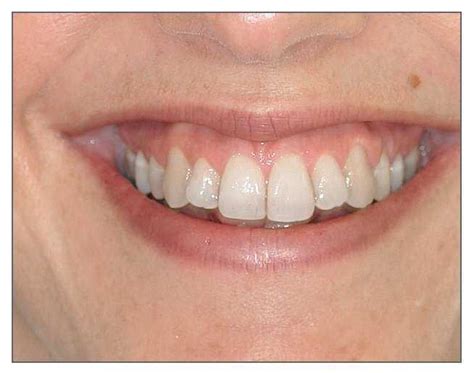

Mujer joven con una sonrisa agradable. Sonrisa ideal.

Una sonrisa estética o agradable está comprendida por tres componentes primarios: los dientes, el marco labial y la plataforma gingival. La sonrisa ideal, estética y agradable presenta las siguientes características:

- Mínima exposición gingival.

- Exposición simétrica y armónica entre la línea gingival superior y el labio inferior.

- Tejido gingival sano que rellena todos los espacios interproximales.

- Armonía entre los segmentos anterior y posterior (principio de graduación).

- Dientes con correcta anatomía y proporciones (forma y posición).

- Color y tono adecuado de los dientes.

- Labio inferior paralelo a los bordes incisales de los dientes anterosuperiores y a una línea imaginaria que transcurre por los puntos de contacto de estos dientes.